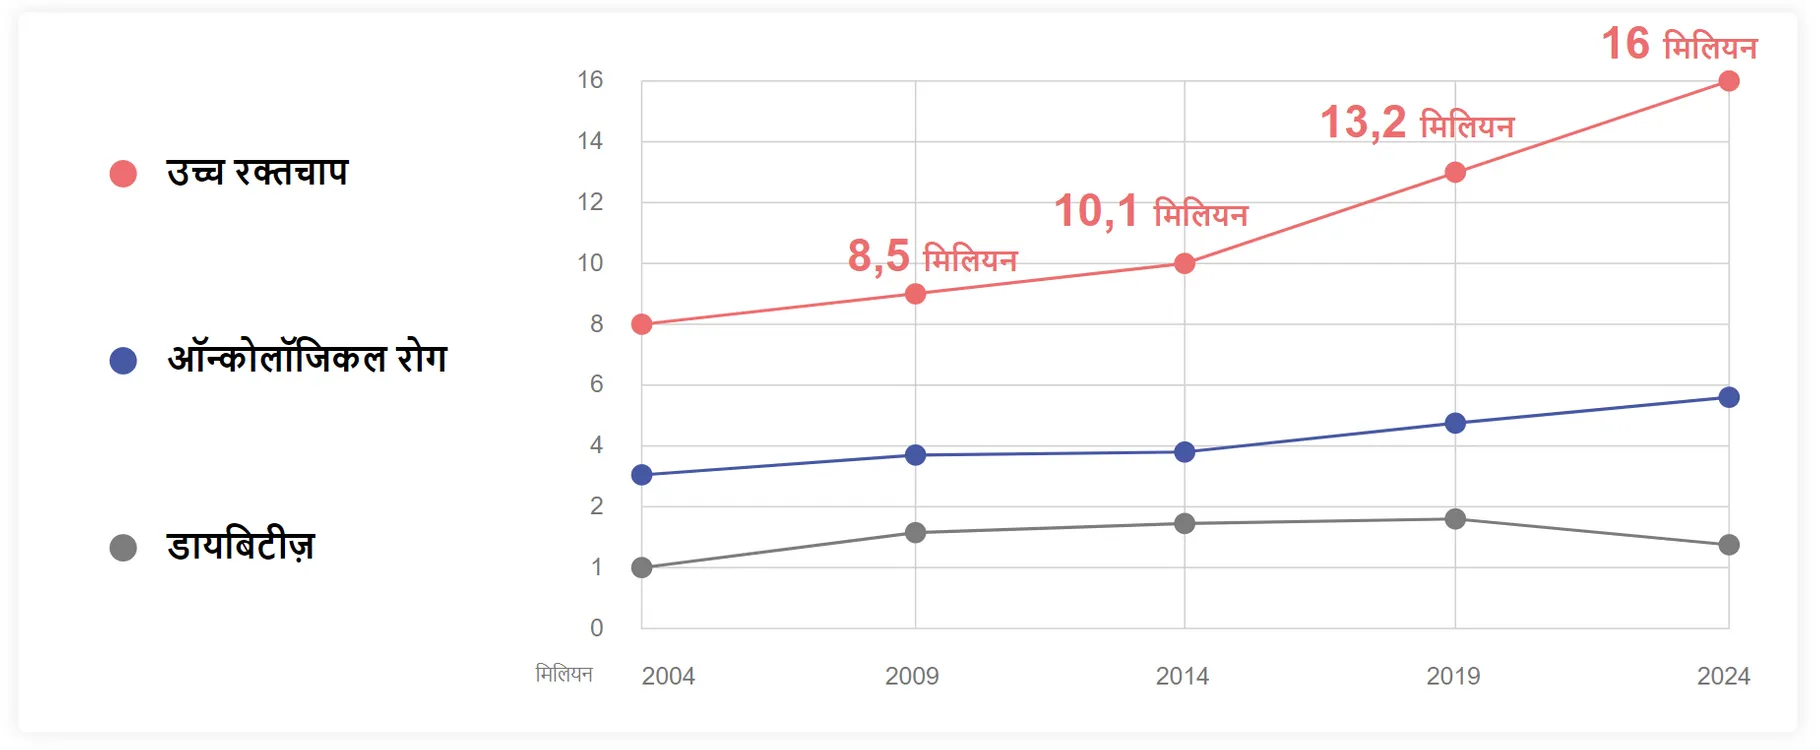

उच्च रक्तचाप एक वर्ष में लाखों लोगों को मारता है!

हाई ब्लड प्रेशर से पीड़ित होना जान के लिए खतरा है!

हाई ब्लड प्रेशर से पीड़ित होना जान के लिए खतरा है!

हाई ब्लड प्रेशर से पीड़ित होना जान के लिए खतरा है!

हाई ब्लड प्रेशर से पीड़ित होना जान के लिए खतरा है!

हाई ब्लड प्रेशर से पीड़ित होना जान के लिए खतरा है!

हाई ब्लड प्रेशर से पीड़ित होना जान के लिए खतरा है!

हाई ब्लड प्रेशर से पीड़ित होना जान के लिए खतरा है!

हाई ब्लड प्रेशर से पीड़ित होना जान के लिए खतरा है!

हाई ब्लड प्रेशर से पीड़ित होना जान के लिए खतरा है!

हाई ब्लड प्रेशर से पीड़ित होना जान के लिए खतरा है!

हाई ब्लड प्रेशर से पीड़ित होना जान के लिए खतरा है!

हाई ब्लड प्रेशर से पीड़ित होना जान के लिए खतरा है!